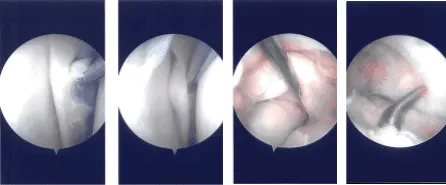

Intraoperative Arthroscopy Images